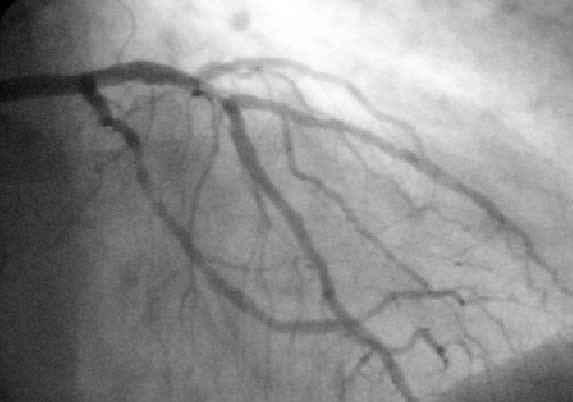

Protected percutaneous coronary intervention, abbreviated as Protected PCI, is a heart procedure that involves a ventricular assist device that is used in order to treat patients with cardiovascular disease, including advanced heart failure.

During a protected percutaneous coronary intervention (Protected PCI) procedure, "the Impella 2.5 heart pump helps maintain a stable heart function by pumping blood for the heart. This gives a weak heart muscle an opportunity to rest and reduces the heart’s workload, preventing the heart from being overstressed by the procedure as coronary artery blockages are repaired". Deborah Moore, the Director of Interventional Cardiology at Florida Hospital Zephyrhills, stated that protected PCI is beneficial in patients who are "inoperable or non-candidates for stents and angioplasty." The Impella 2.5, used in protected PCI, "received FDA approval for elective and urgent high-risk PCI procedures in March 2015, following its 510(k) clearance in 2008" and as a percutaneous hemodynamic support device, it was deemed "safe and effective for patients with complex coronary disease, depressed ejection fraction, other co-morbidities, and who have been refused for surgical treatment." The PROTECT II Study, published in Circulation found that the "Impella 2.5 provided superior hemodynamic support in comparison with IABP, with maximal decrease in cardiac power output from baseline of −0.04±0.24 W in comparison with −0.14±0.27 W for IABP (P=0.001)." Hospitals such as Detroit Medical Center, and organizations such as the Society of Cardiovascular Angiography and Interventions, have featured lectures including "The New Era of Protected PCI: Treating Elective and High-Risk PCI Patients with Impella 2.5", and "Expanding your Patient Practice with Protected PCI: Treating the Most Complex Patients" in order to educate physicians on using protected percutaneous coronary intervention, respectively.